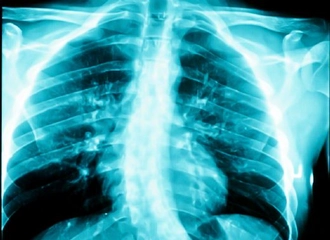

Her bir tür, farklı tedavi yaklaşımları gerektirebilir. İdiyopatik skolyoz, genellikle ergenlik döneminde ortaya çıkar ve tedavi edilmediğinde ciddi sorunlara yol açabilir. Skolyozun TanısıSkolyozun tanısı genellikle fizik muayene ve görüntüleme yöntemleri ile konur. Doktor, hastanın duruşunu değerlendirir ve gerekirse röntgen çekimi yapar. Röntgen, omurganın eğilimini ve açılarını belirlemeye yardımcı olur. Skolyoz Tedavi YöntemleriSkolyoz tedavisinde kullanılan başlıca yöntemler şunlardır: